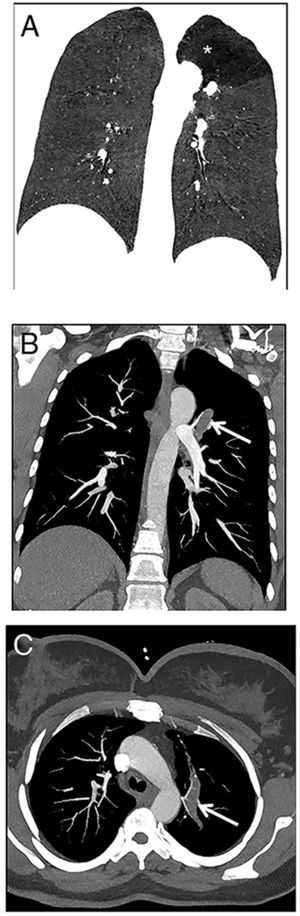

A 22-year-old woman was referred to our emergency radiology unit with sudden onset of shortness of breath and left-sided chest pain. The chest radiography revealed left hilar tubular opacite (arrow) and hyperaeration (asterisk) in the upper zone of the left lung (Fig. 1). The contrast enhanced computed tomography (CT) showed a non-contrast enhancing tubular mass that was seen extending from the left hilum, with surrounding hypoattenuation of the apicoposterior segment of the left upper lobe (asterisk), a finding indicative of hyperinflation (Fig. 2A). There was also no connection between the non-contrast tubular mass (arrows) and pulmonary artery of the apicoposterior segment in the left upper lobe (Fig. 2B–C). CT findings were also including mucocele and occlusion of the bronchus central to the mucocele. CT results (mucocele with hyperaeration of the adjacent lung parenchyma) were considered pathognomonic for bronchial atresia. Surgical treatment was no performed because the patient refused operation.

The reformat coronal CT at maximum inspiration (A) shows a non-contrast enhancing tubular lesion with surrounding hypoattenuation of the apicoposterior segment of the left upper lobe (asterisk), a finding indicative of hyperinflation. The coronal CT scan also demonstrates aerial trapping in the apicoposterior segment of the left upper lobe. The contrast enhanced maximum intensity projection images (B and C) reveal no connection between the non-contrast tubular lesion (arrows) and pulmonary artery of the apicoposterior segment in the left upper lobe.